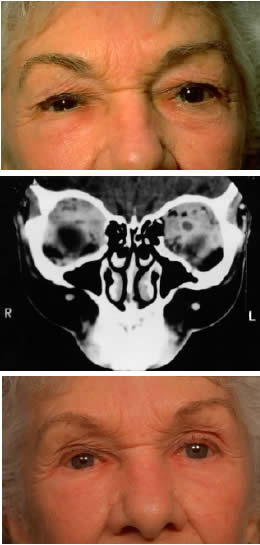

The clinical signs of squamous cell carcinoma (mean, 1 year) develop faster than the signs of basal cell carcinoma, consisting of focal hyperkeratotic lesions that slowly extend and ulcerate. They are more common at the lid margin and in the lower lid versus the upper lid, by a ratio of 1.4:1.56 Rarely, papillary forms may be seen. Orbital extension of squamous cell carcinoma is usually preceded by a history of chronic and repeated recurrence of lesions following treatment or long-term neglect by the patient (Fig. 7). Once the orbit is invaded, the tumor tends to spread along fascia and fatty planes relatively rapidly compared with basal cell carcinoma. Perineural invasion may occur and is associated with pain or ophthalmoplegia (Fig. 8).57–60 Also in contrast to basal cell carcinoma, squamous cell carcinoma is capable of metastasis, usually to the regional preauricular or submandibular lymph nodes. The incidence of regional spread varies from 1% to 21%, but is generally closer to the lower figure. In a review of large series documented in the literature, the overall mortality rate was found to be approximately 15%.56 Management of squamous cell carcinoma of the lid is usually surgical, with care being taken to obtain adequate controlled margins with the use of frozen sections or Mohs' technique. Fitzpatrick and associates61 reported a control rate of 93% with radiotherapy; however, squamous cell carcinoma is thought to be less sensitive to radiotherapy than basal cell carcinoma, so higher doses are usually recommended. For deep orbital invasion, radical therapy is indicated; this may constitute either exenteration or radical radiotherapy, according to the circumstances outlined in the discussion on basal cell carcinoma.

Fig. 7. A 61-year-old chronic alcoholic man presented with a fungating, putrefying, left temporal mass(inset) that extended into the adjacent orbit and flattened the globe, as shown on coronal CT scan. It proved to be a squamous cell carcinoma of the skin associated with cervical and mediastinal adenopathy. He underwent radical local radiotherapy, which led to regression of the local lesion. (Rootman J, Ragaz J, Cline R, Lapointe JS: Metastatic and secondary tumors of the orbit. In Rootman JR (ed): Diseases of the Orbit: A Multidisciplinary Approach, pp 405–427. Philadelphia, JB Lippincott, 1988.)

Fig. 8. A 73-year-old man treated 3 years previously with excision of a squamous cell carcinoma in the left supraorbital region had recurrence of tumor, which was again excised. He developed progressive pain and tingling in the forehead, vertical diplopia, and finally general malaise lasting 18 months, ultimately requiring hospitalization. He was treated with corticosteroids for presumed Tolosa-Hunt syndrome, showed minimal improvement, and was discharged. Over a 2-month period, he developed decreased vision, ptosis, and bulging of the eye. On presentation he had vision of 20/80 with a relative afferent pupillary defect. There was hypesthesia in the distribution of cranial nerve V1 and hyperesthesia in V2. He had a palpable fixed cord in the forehead in the distribution of the supraorbital nerve, complete ptosis, ophthalmoplegia, and 7 mm of proptosis (A). CT scan showed local infiltration along the supraorbital nerve (B, arrow), with extension of a soft tissue mass along the orbital roof to the orbital apex (C), through a widened superior orbital fissure, and into the cavernous sinus (D). An orbital biopsy revealed cords of squamous cells (E) (H & E, × 80) and evidence of infiltration inside a small branch nerve sheath (F) (H & E, × 80). A single fraction of 10 Gy was given as palliative treatment for pain control.